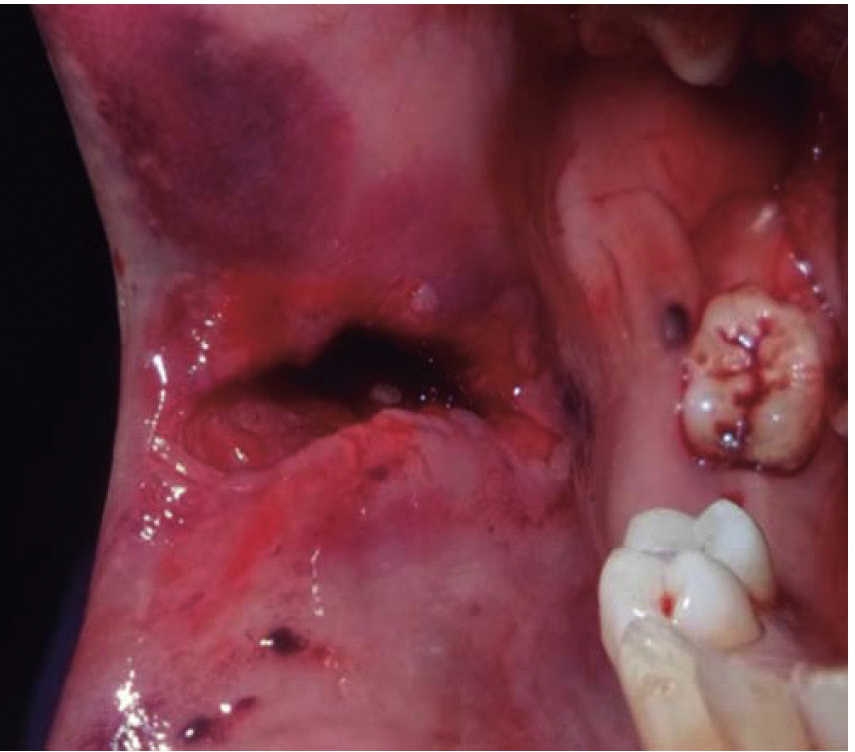

Masculino de 30 años con diagnóstico de fractura de cuerpo mandibular izquierdo por proyectil de arma de fuego. Sufre agresión en una riña al salir de un centro de diversión nocturna y es disparado a cuatro metros de distancia. A la exploración se presenta edema a nivel cervical, tercio medio e inferior facial, orificio de entrada en región geniana izquierda y orificio de salida a nivel submandibular derecho (Figura 4). Intraoralmente con herida en proceso alveolar mandibular en línea de fractura y ausencia de piezas dentales (Figura 5). Se inicia bajo anestesia general tratamiento con estabilización de la vía aérea mediante traqueotomía. A nivel local se realiza desbridamiento de bordes de herida, lavado con jabón quirúrgico, solución fisiológica y sutura de herida. Al terminar el tratamiento de tejidos blandos se busca estabilidad inicial oclusal con arco barra tipo Erich. El paciente permanece hospitalizado bajo un esquema terapéutico de inmunización, antibiótico y analgésico.

En los tres casos presentados se inicia con valoración cardiopulmonar, manejo de vía aérea, control hemodinámico, ventilación, discapacidad neurológica y daños específicos.9-11 Con la exploración física determinamos la extensión de daño en los tejidos, presencia de orificios de entrada y salida para descartar la presencia de bala al interior en una cavidad o tejido (caso 2). El manejo maxilofacial se inicia con desbridaje conservador, lavado, extracción de restos radiculares, sutura y estabilización oclusal. La reducción y fijación de las fracturas (caso 1 y 3) se realizó en un segundo acto quirúrgico con placas de reconstrucción. En los casos expuestos se observó una buena evolución, una cicatriz ósea favorable y la necesidad de continuar con una rehabilitación oral mediante prótesis o implantes osteointegrados. Las complicaciones y secuelas son comunes y surgen por lo general a causa de la severidad de las lesiones iniciales, retraso en el tratamiento por riesgo vital o estado sistémico del paciente.